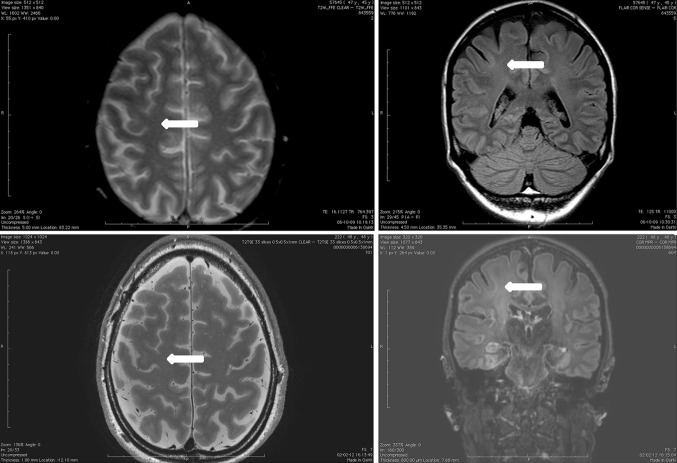

In the eight patients in whom 3 T MRI was available, 7 T MRI depiction scored significantly better than 3 T MRI for blurring (p < 0.01), abnormalities of internal structure (p < 0.01) and demarcation of transition to normal cortex (p < 0.02) (Fig. 5) on T2 and for abnormalities of internal structure (p < 0.04) on FLAIR. Although not statistically significant, 7 T MRI tended to be superior to 3 T on another 7 out of 14 scored items (2 sequences compared, with 7 features analysed in each comparison) 3 T MRI tended to be superior to 7 T on none of the 14 items (Table 3). When combining all seven analysed characteristics on T2 and FLAIR in each individual patient, 7 T scored better than 3 T (Table 4).

Fig. 5.

Comparison between 3 (top) and 7 (bottom) T images of a patient with known FCD right hand knob to deep-of-the-sulcus. From left to right T2, FLAIR